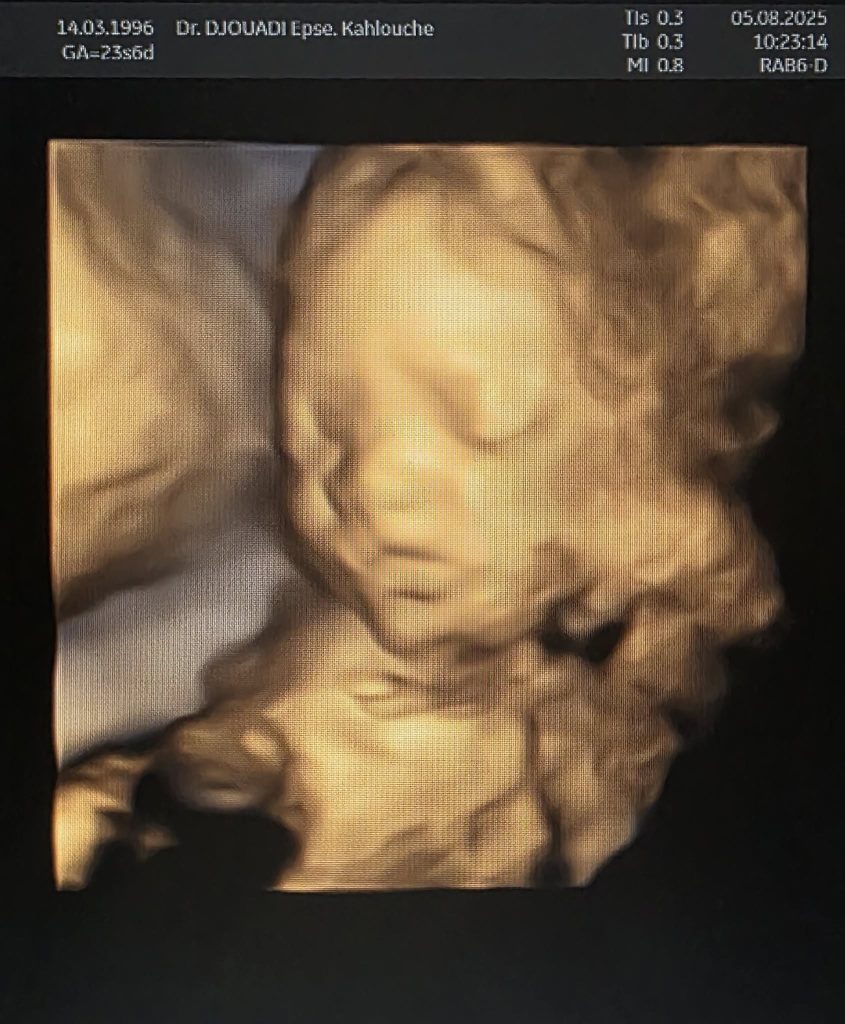

| Echographie obstétrique (3D – 4D) | الموجات فوق الصوتية ثلاثي الأبعاد – رباعي الأبعاد للحامل |